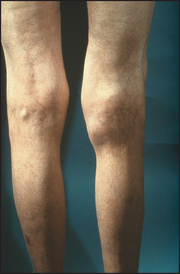

Joint pain may be well localised if there is inflammation close to the skin, but deeper joint abnormalities may cause pain to be referred. The areas where joint pain is felt correspond to the innervation of the muscle attached to that joint—the myotome. For example, the glenohumeral joint of the shoulder and the posterior scapular muscles are supplied from C5 and C6, so pain over the shoulder or scapula may arise from any structure supplied from these nerve roots—including the shoulder muscles and joints but also the C5 and C6 segments of the spine. Figure 24.1 shows typical synovial joints affected in rheumatoid arthritis.

Figure 24.1 Typical synovial joints affected in rheumatoid arthritis (symmetrical, arms and legs, large and small joints) (Courtesy of Glenn McCulloch)